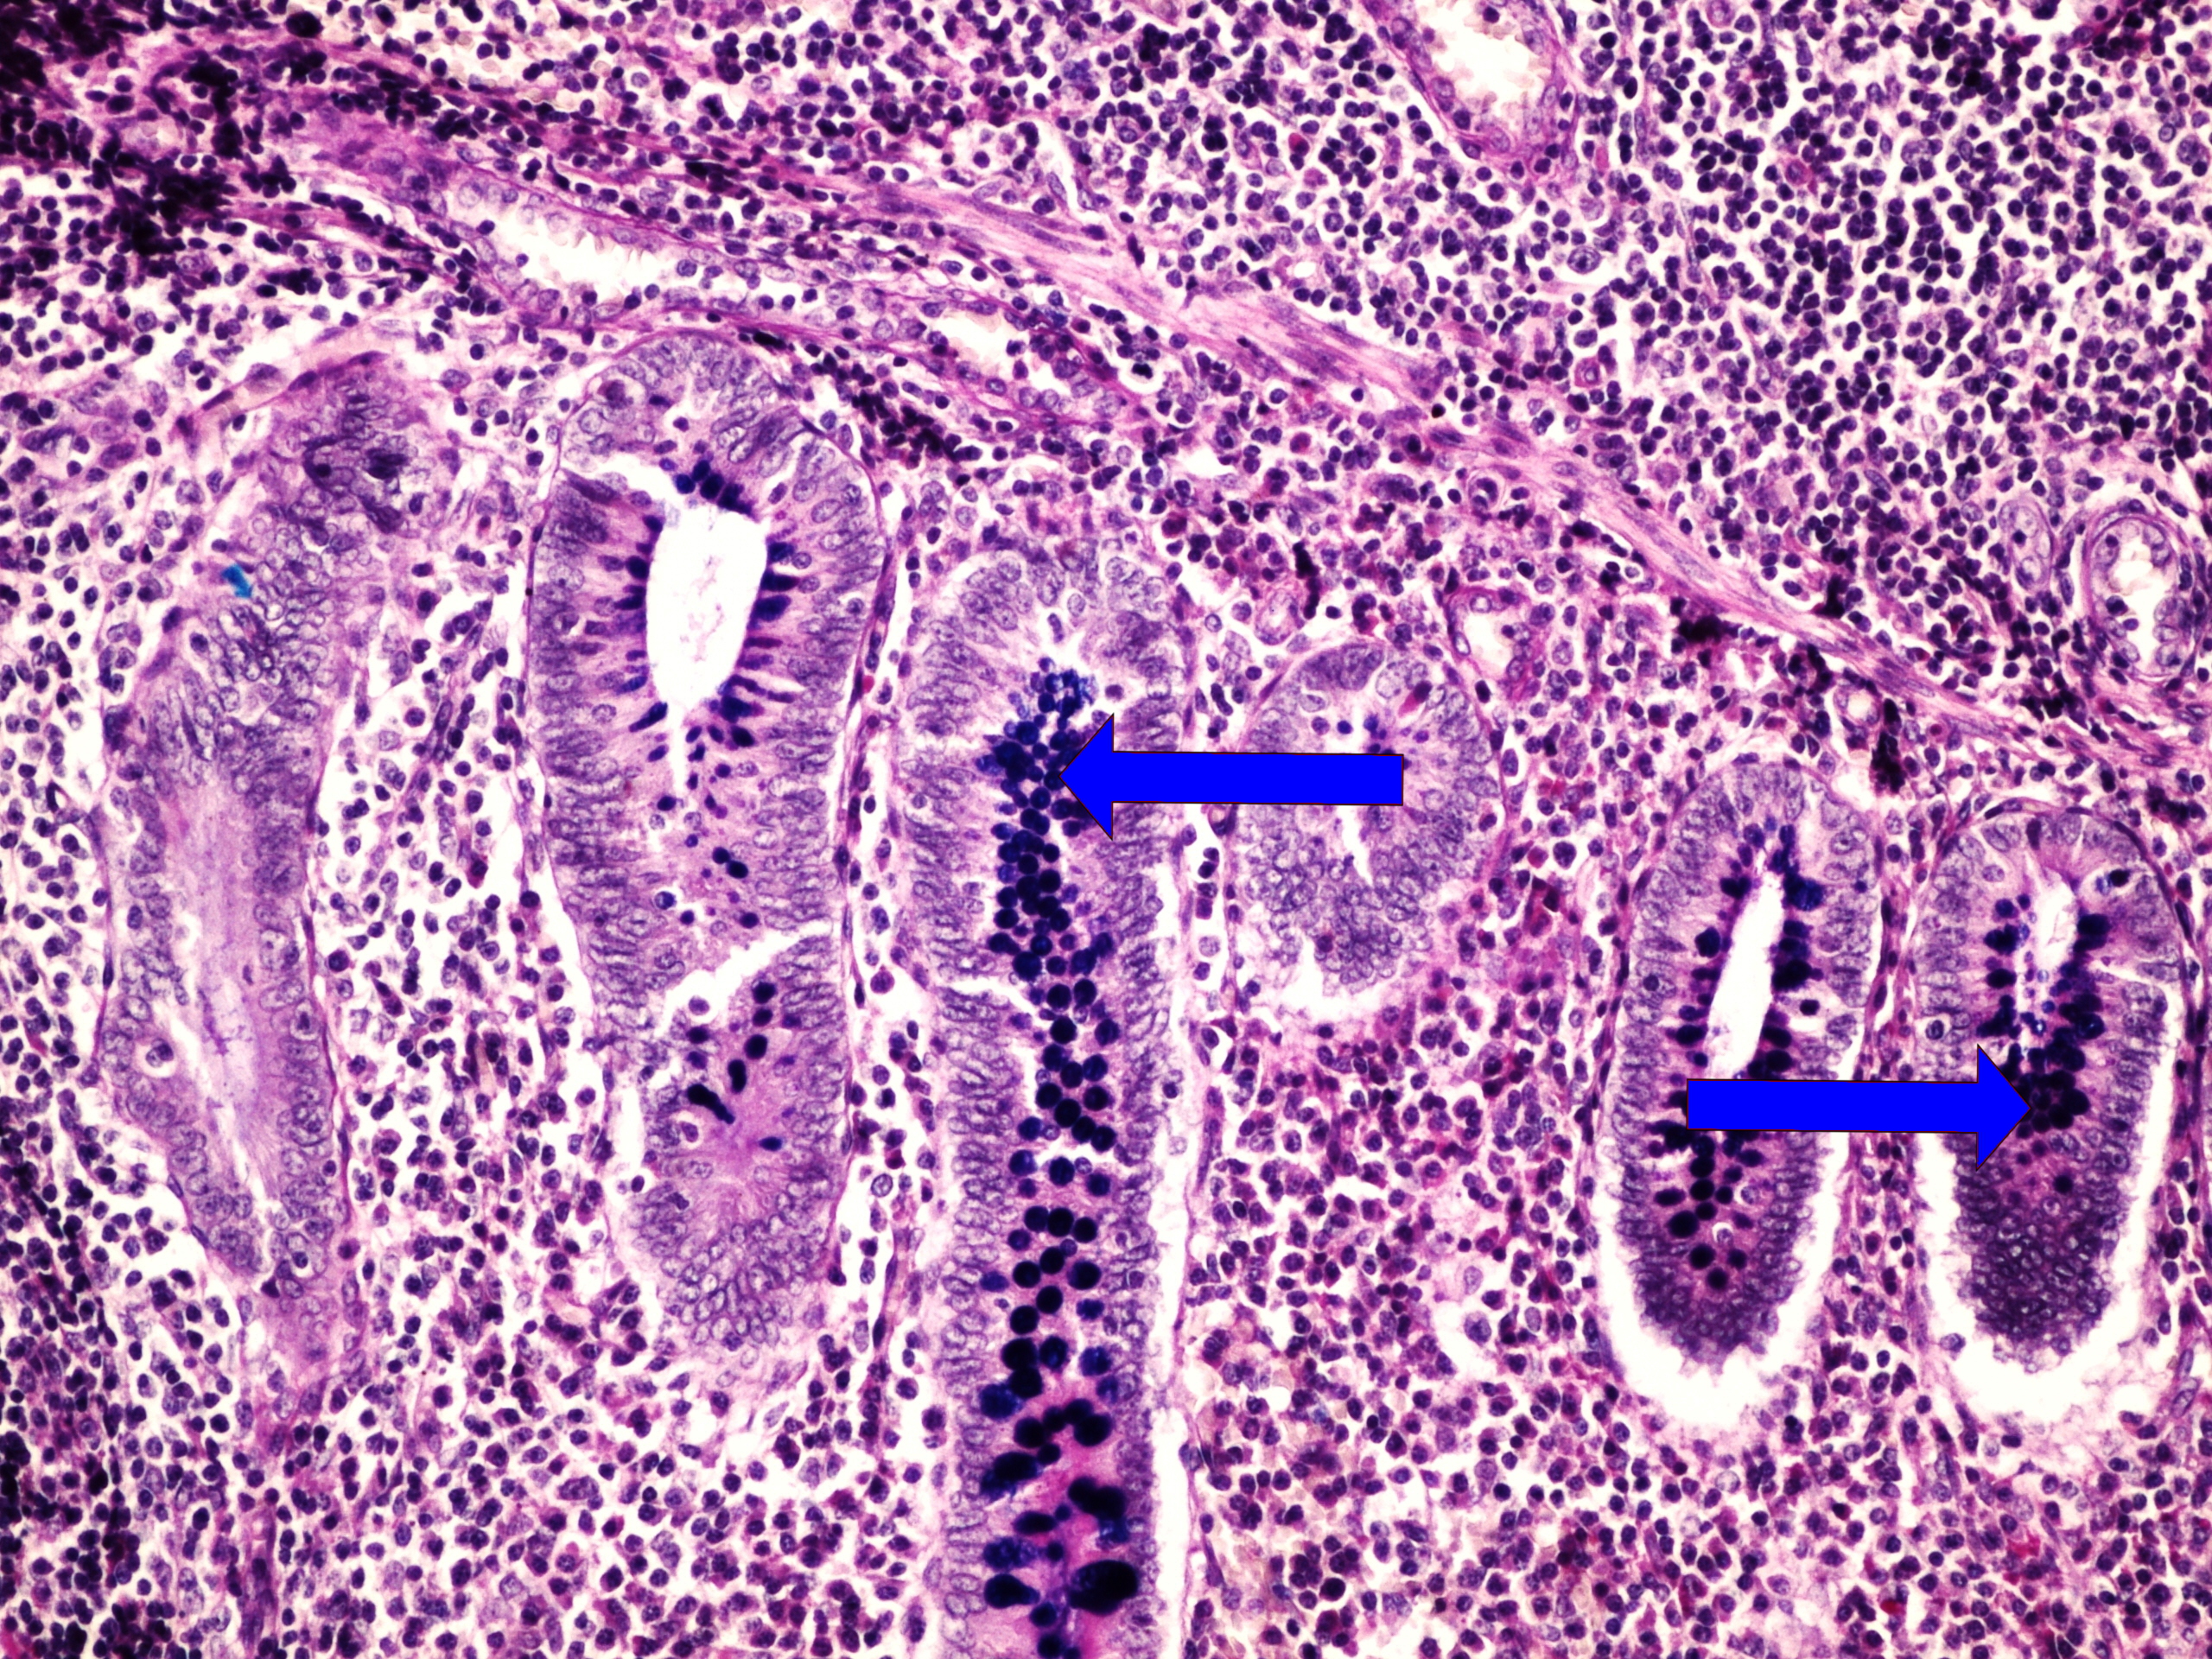

Preparát č.15 a č.16 - barvení dle Mowryho (appendix vermiformis)

Struktury

- lymfatický folikul se zárodečným centrem

- intracytoplazmatické hlenové vakuoly v buňkách výstelky sliznice